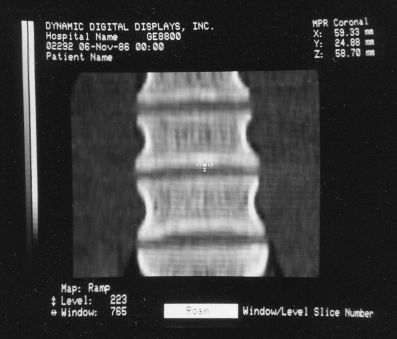

Shading of the rendered objects is essential to the perception of 3-D depth in a static display of a single image (no stereo). Motion parallax also contributes to this but only if the update rate is high enough. The VPP only had "depth shading", whereby each pixel's value was modified by distance from the viewer. Subsequent machines used "gradient shading" which also calculated the local rate-of-change of the surface to modulate the pixel intensity. While this was not photo-realistic, the overall effect was quite satisfactory at a much lower computational cost. And with the tri-linearly interpolated voxels, the result was actually quite impressive.

Shading for Ray Tracing (Portion of Cervical Spine)

While the VPP and Voxelscopes I and II rendered "back-to-front" to implement hidden surface removal, the redesigned VoxelQ hardware was optimized for ray tracing with volume rendering capabilities. VQ projected a ray from each pixel on the display back through the object and was able to perform computations along the way. An innovative sub-voxel search algorithm rendered much more realistic surfaces using relatively simple surface shading algorithms. Even Anthony was impressed with the image quality when this technique was first simulated in software with the intent of incorporating it into the microcode - and he was most familiar what else was being done in software, which could render the best images since there were fewer time constraints. In addition to hidden surface removal and gradient shading, this approach supports various forms of transparency with perspective enabling the simulation of X-ray views ("reprojection") as well as rendering translucent organs. Many of the changes were implemented in microcode with relatively small changes to the actual hardware. But the key innovation that differentiated VoxelQ from the machines before it was the "Object Resampling Memory" (ORM) which generated tri-linearly interpolated voxel data based on full 3-D coordinates. Essentially, the eight adjacent voxels closest to the specified coordinate in the original dataset were accessed simultaneously and an interpolated result was computed auto-magically. For successive coordinates that were close together (as they would be for ray tracing), the effective throughput could approach 10 million tri-linearly interpolated voxels per second. The ORM was the only totally new custom board and replaced the MicroVAX memory.